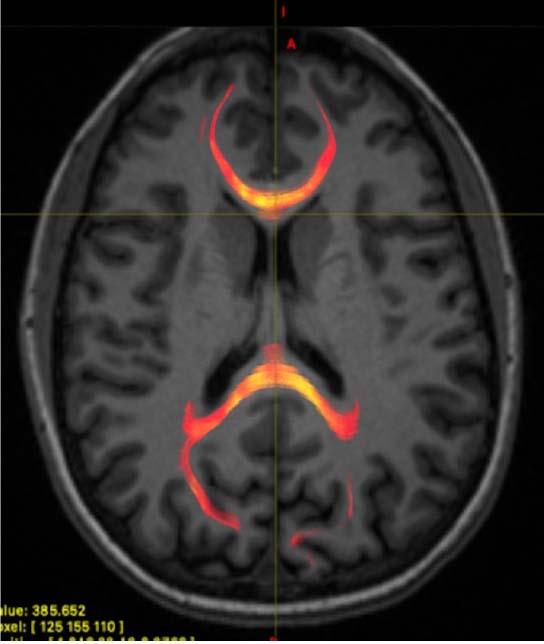

image: MRI image from a mild traumatic brain injured patient demonstrating corpus callosum fiber tractography, which is a 3D reconstruction of white matter fibers. This image specifically provides information on the axonal water fraction, which was one of the compartment diffusion metrics analyzed.

To learn more, researchers at New York University (NYU) School of Medicine in New York City compared the condition of the corpus callosum in 36 patients with recent concussion to that of 27 healthy controls. They studied the participants' brains with two innovative advances, including an MRI technique that uses measures of water diffusion to provide a microscopic view of the brain's signal-carrying white matter.

"Looking at how water molecules are diffusing in the nerve fibers in the corpus callosum and within the microenvironment around the nerve fibers allows us to better understand the white matter microstructural injury that occurs," said study co-author Melanie Wegener, M.D., resident physician at NYU Langone Health in New York City.